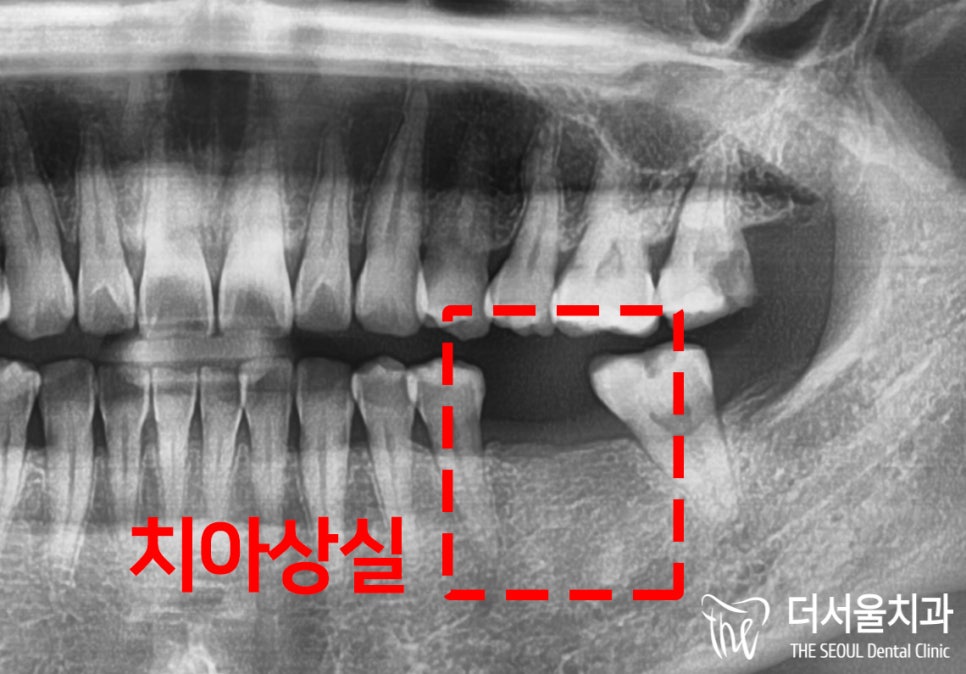

실제 구강 내를 보면

말씀하셨던 곳이 비어져 있는 것을

확인할 수 있었습니다.

신경관이나 주변 조직 등

별다른 문제들은 나타나지 않았습니다.

여기서 한 가지 살펴봐야 될 것은

치조골의 양이 충분한지입니다.

치아가 상실되고 오랜 시간 방치를 하게 되면

안에 있는 치조골 또한 소실이 일어나게 됩니다.

결국에는 최소절개임플란트 를 심을 수 없을 정도로

골의 양이 모자라게 되는 것인데요.

다행히 이 환자의 경우는

비교적 젊은 연령대라 그런지

생각보다 소실도가 크지 않았습니다^^